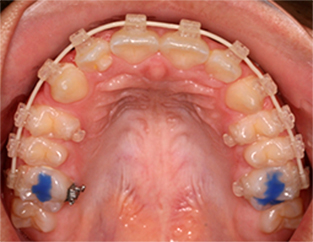

Ortodoncias